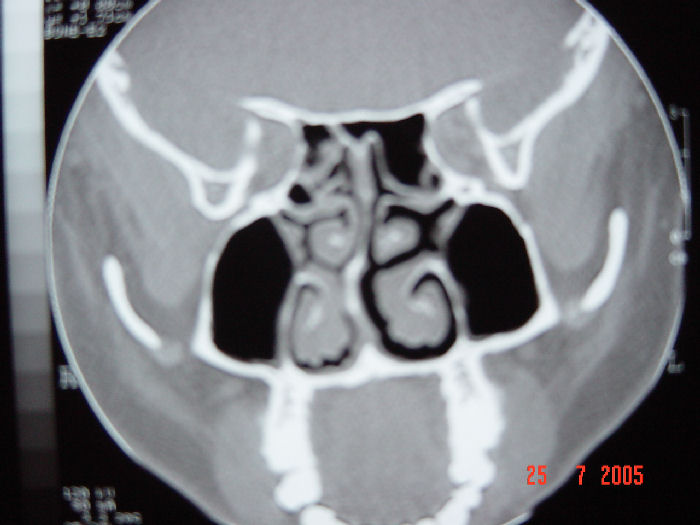

Tomografía de Desviación del Tabique Nasal

Desviación Septal

Desviación Septal y Rinosinusitis Crónica